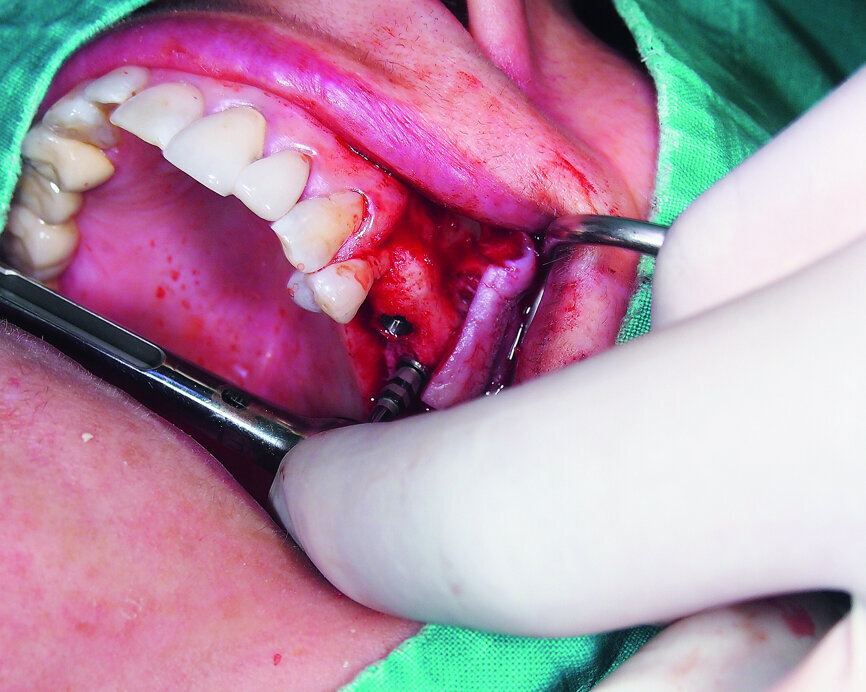

Fig. 16: Mandibular ridge splitting with vertical cuts.

Fig. 17: Creation of space in between the buccal and lingual lamina with the intact attached periosteum on the buccal.

A demonstration of this technique is shown in Figures 13 to 20. This case presents an elderly woman who had lost her teeth in the lateral mandible decades ago. Being a healthy non-smoker with good oral hygiene, no history of periodontal disease and low masticatory forces, she was an adequate candidate for bone grafting together with implant placement. The future restorative margins allowed the usage of ridge splitting (Figs. 13 & 14). Therefore, we opted for a ridge split with vertical releases carried out utilising a partial-thickness flap. The periosteum was left attached in order not to impede the perfusion of the buccal plate (Fig. 15). After ridge splitting, the buccal and lingual plates were separated with the use of bone spreaders (Split-Control Plus, Meisinger) to allow the placement of two GC Aadva Standard implants, one of 3.3 mm in diameter and 8.0 mm in length and the other measuring 4.0 mm in diameter and 8.0 mm in length (Figs. 16–18).